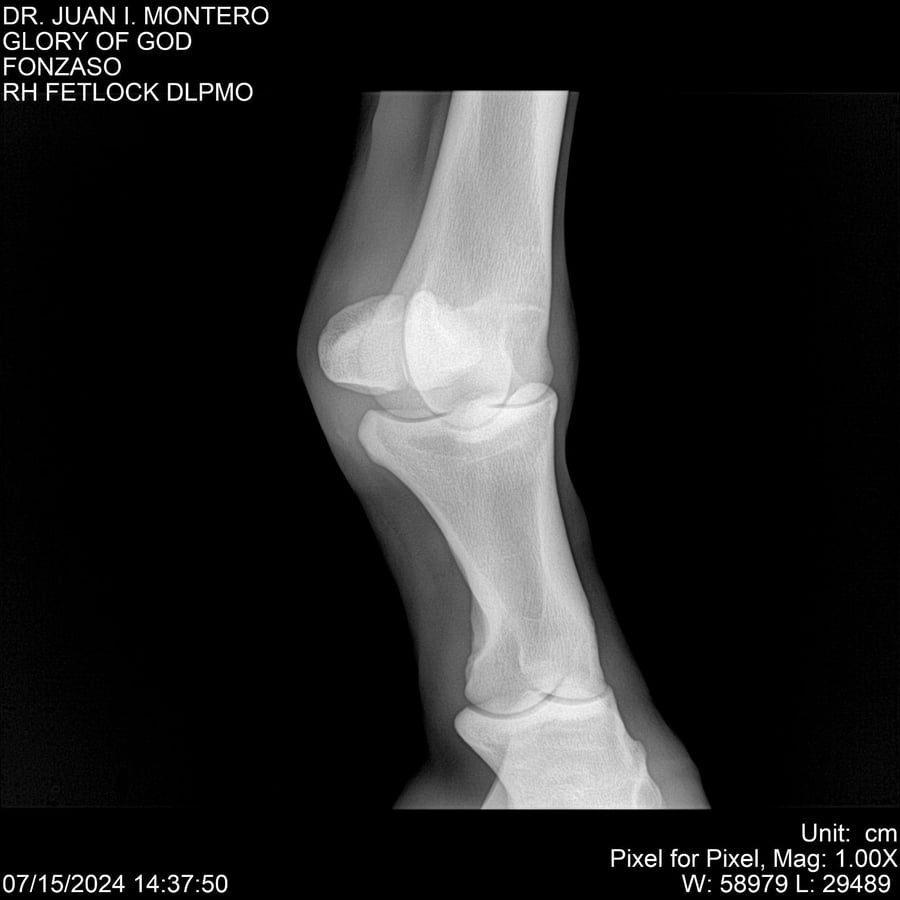

LOTE 10, GLORY OF GOD 🔥 🔥 🔥 Lote Anterior Volver al remate Lote Siguiente Ficha Contacto Montevideo - Ficha del Lote Identificador: #281389 Categoría: Yeguarizos Montevideo - 115 Visualizaciones ClicData Contacto Empresa: Abelenda N. R., Walter Hugo Nombre*: Teléfono* : E-mail* : Mensaje Enviar Registrese gratis Este contenido Exclusivo está disponible sólo para usuarios registrados Ingresar